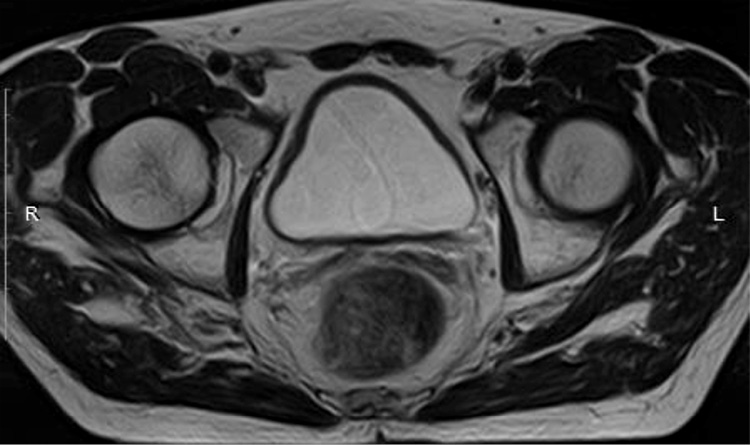

МРТ органов большого таза – ОБП (14.10.2021): По заднеправой стенке мочевого пузыря, в том числе на уровне устья правого мочеточника, визуализируется опухолевое образование неправильной формы с нечеткими неровными контурами со смешанным характером роста. Размер эндофитного компонента 40×21 мм, размер экзофитного компонента – 8×6 мм. Образование вовлекает всю толщу стенки с распространением процесса в паравезикальную клетчатку. Получена МР-картина Cr. мочевого пузыря с выходом процесса за пределы стенки. Удвоение правого мочеточника, уретероэктазия справа. Гиперплазия предстательной железы с наличием участка измененного МР-сигнала в транзиторной зоне левой доли (PI-RADS-4). Метастазы в кости таза. В сравнении с данными исследованиями от 27.08.2021 отмечается отрицательная динамика (рис. 2).

Рис. 2. МРТ ОМТ от 14.10.2021: опухолевое образование неправильной формы с нечеткими неровными контурами со смешанным характером роста. Размер эндофитного компонента – 40×21 мм, размер экзофитного компонента – 8×6 мм.

Fig. 2. Pelvic magnetic resonance imaging (MRI) dated 14.10.2021: tumor mass of irregular shape with ill-defined uneven contours with a mixed growth pattern. The size of the endophytic component is 40×21 mm, and the size of the exophytic component is 8×6 mm.

Рис. 4. МРТ ОМТ от 14.10.2021 в сравнении с МРТ от 27.12.2021. Состояние после 3-го курса лекарственного лечения по схеме EP: опухолевое образование неправильной формы с нечеткими неровными контурами со смешанным характером роста размерами до 14×11 мм с внутрипросветным компонентом.

Fig. 4. Pelvic MRI dated 14.10.2021 in comparison with MRI dated 27.12.2021. State after the 3rd course of drug treatment according to the EP regimen: tumor mass of irregular shape with ill-defined uneven contours with a mixed growth pattern up to 14×11 mm with an intraluminal component.